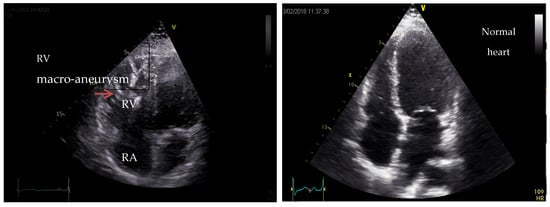

8. Arrhythmogenic Cardiomyopathy (ACM)